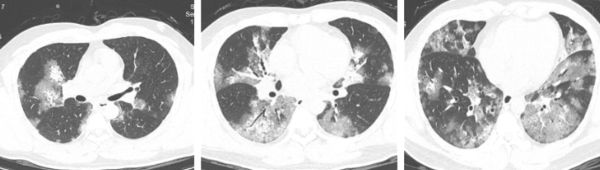

【流感/甲流/甲型流感/大S/徐熙媛/白肺】內地一名男子早前出現咳嗽,起初以為只是感冒,求診後證患甲型流感且出現「白肺」。網傳因流感併發肺炎病逝的台灣女藝人大S(徐熙媛),生前雙肺亦呈白肺,有醫生形容等同「病人被自己的痰淹死」。

數天後,劉先生還出現氣喘情況,遂趕緊到醫院就診,醫生為他進行流感核酸檢測和胸部電腦斷層掃描(CT)檢查,結果顯示他感染甲型流感,兩肺有非常嚴重的「磨玻璃樣」滲出,即出現「白肺」。

杭師大附屬醫院呼吸與危重症醫學科呂群醫生分析,以往高致病性禽流感、新冠病毒感染等病毒性肺炎,在病情嚴重時都有可能引發白肺現象,但像劉先生這樣因流感而導致的重症流感病例,並進展到出現顯著肺部病變乃至「白肺」的程度,相對較為罕見,「劉先生的氧飽和度下降至85%,所幸在醫護人員的努力下,他的病情逐漸穩定」。

至於網傳大S臨終前CT影像顯示雙肺呈白肺狀態,送院時血氧濃度已降到89%(正常為95%至100%)。台北市立聯合醫院陽明院區胸腔內科醫生蘇一峰解釋,「大白肺」即嚴重肺炎導致呼吸困難,等於「病人被自己的痰液水腫活活淹死」,如一直未有處理缺氧狀態,可能半天數小時內,因心跳呼吸停止死亡。